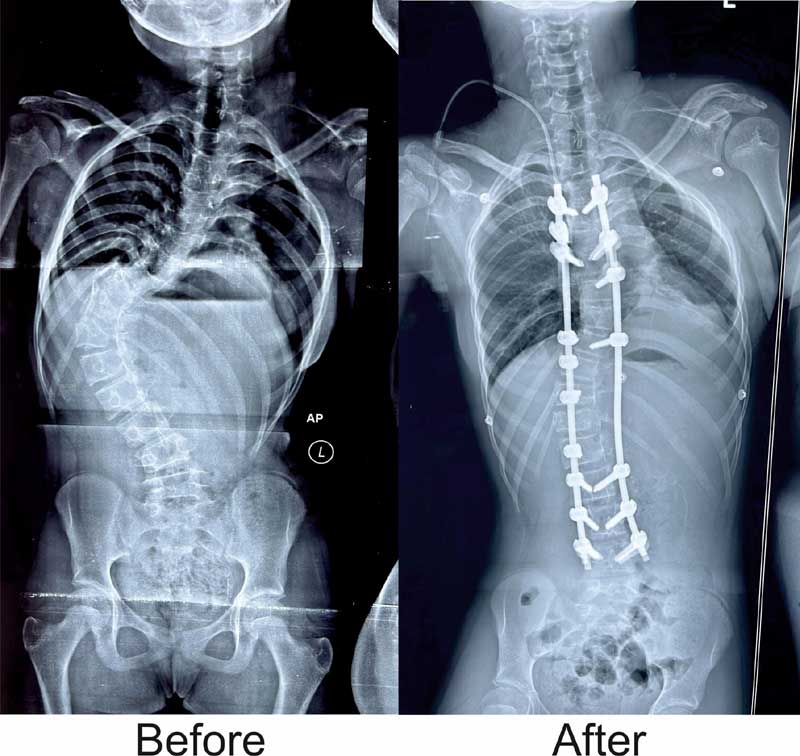

ଭୁବନେଶ୍ୱର: ମେରୁଦଣ୍ଡ ବଙ୍କା ହୋଇଯାଇଥିବା ଜନୈକା ବାଳିକାଙ୍କଠାରେ ସଫଳ ଅସ୍ତ୍ରୋପଚାର ଦ୍ୱାରା ଏହାକୁ ସଳଖ କରି ପାରିଛନ୍ତି କିମ୍ସର ଡାକ୍ତର । ସ୍କୋଲିଓସିସ୍ ନାମକ ଗୁରୁତର ମେରୁଦଣ୍ଡ ସମସ୍ୟା ସହ ଦୀର୍ଘ ଦିନ ଧରି ସଂଘର୍ଷ କରୁଥିବା ଏହି ବାଳିକାଙ୍କ ଅଭିଭାବକ ବହୁ ଖ୍ୟାତି ସମ୍ପନ୍ନ ଡାକ୍ତରଖାନାରୁ ନିରାଶ ହୋଇ ଶେଷରେ କିମ୍ସ ଡାକ୍ତରଙ୍କ ସହ ପରାମର୍ଶ କରିଥିଲେ । ଅସ୍ଥିଶଲ୍ୟ ବିଶେଷଜ୍ଞ ତଥା ସ୍ପାଇନ୍ ସର୍ଜନ ଡା ଜିତେନ୍ଦ୍ର କୁମାର ରାଉତ ରୋଗୀଙ୍କୁ ଦେଖିବା ପରେ ଏହା ‘ଇଡିଓପାଥିକ ସ୍କୋଲିଓସିସ୍’ ନାମକ ଏକ ପ୍ରକାର ମେରୁଦଣ୍ଡ ସମସ୍ୟା ବୋଲି ଜାଣି ତୁରନ୍ତ ଅସ୍ତେ୍ରାପଚାର ପାଇଁ ପରାମର୍ଶ ଦେଇଥିଲେ । ନିଶ୍ଚେତକ ବିଭାଗର ଡା ସଞ୍ଜୀବ ଗିରି ଓ ରାଜ ମୋହନଙ୍କ ସହଯୋଗରେ ସ୍ପାଇନ୍ ସର୍ଜନ ଡା ରାଉତ ଏହି ଅସ୍ତେ୍ରାପଚାର କରିଥିଲେ । ବାଳିକାଙ୍କ ମେରୁଦଣ୍ଡ ଇଂରାଜୀ ଅକ୍ଷର ‘ଏସ୍’ ଆକୃତିର ହୋଇଯାଇଥିଲା, ଯାହା ଭବିଷ୍ୟତରେ ତାଙ୍କ ପାଇଁ ଆହୁରି ଅନେକ ସମସ୍ୟା ସୃଷ୍ଟି କରିଥାନ୍ତା ବୋଲି ଡା. ରାଉତ ପ୍ରକାଶ କରିଛନ୍ତି । କିମ୍ସରେ ଦକ୍ଷ ଡାକ୍ତର, ଉନ୍ନତ ଜ୍ଞାନକୈଶଳ ଓ ଯନ୍ତ୍ରାଂଶ ଉପଲବ୍ଧ ଯୋଗୁଁ ଏଭଳି ବିରଳ ମେରୁଦଣ୍ଡ ଅସ୍ତେ୍ରାପଚାର ସମ୍ଭବ ହୋଇପାରିଲା । ସେ ବର୍ତ୍ତମାନ ସମ୍ପୂର୍ଣ୍ଣ ସୁସ୍ଥ ହୋଇଛନ୍ତି । କିଛି ଦିନ ବିଶ୍ରାମ ପରେ ସେ ସ୍ୱାଭାବିକ ଜୀବନଯାପନ କରିପାରିବେ ବୋଲି ଡାକ୍ତର ରାଉତ କହିଛନ୍ତି । ସାଧାରଣତଃ ୧୦ରୁ ୧୫ ବର୍ଷ ବୟସ ମଧ୍ୟରେ ଏହି ରୋଗ ଦେଖାଦେଇପାରେ । ତୁରନ୍ତ ରୋଗର ଚିହ୍ନଟ ଓ ଉପଯୁକ୍ତ ସମୟରେ ଏହାର ଚିକିତ୍ସା କରାଗଲେ ଏହି ରୋଗର ଉପଶମ ହୋଇପାରିବ । ଏହା ରୋଗୀର ଆତ୍ମବିଶ୍ୱାସ ଏବଂ ଆତ୍ମସମ୍ମାନକୁ ପ୍ରଭାବିତ କରିପାରେ । ଏପରି ରୋଗୀ ଅନେକ ସମୟରେ ଥଟ୍ଟା ଏବଂ ଉପହାସର ପାତ୍ର ହୋଇଥାନ୍ତି । କମ୍ ବୟସରୁ ହିଁ ଏହାର ଚିକିତ୍ସା କରାଯିବା ଆବଶ୍ୟକ ନଚେତ ବୟସ ବଢ଼ିବା ସହିତ ଏହାର ଚିକତ୍ସା ମଧ୍ୟ ଅଧିକ ଜଟିଳ ହୋଇଯାଇଥାଏ ବୋଲି ଡା. ରାଉତ କହିଛନ୍ତି ।

ସୂଚନାଯୋଗ୍ୟ, ପ୍ରଥମଥର ପାଇଁ ଓଡ଼ିଶାର ଏକ ଘରୋଇ ହସ୍ପିଟାଲରେ ଏଭଳି ଜଟିଳ ମେରୁଦଣ୍ଡ ଅସ୍ତେ୍ରାପଚାର କରାଯାଇପାରିଛି । ଏଭଳି ବିରଳ ଅସ୍ତେ୍ରାପଚାର କରି ‘କିମ୍ସ’ ରାଜ୍ୟର ଉନ୍ନତ ସ୍ୱାସ୍ଥ୍ୟସେବା ପ୍ରଦାନକାରୀ ଅନୁଷ୍ଠାନ ଭାବେ ନିଜକୁ ପ୍ରମାଣିତ କରିପାରିଛି । ଏହି ମେରୁଦଣ୍ଡ ଅସ୍ତ୍ରୋପଚାର ସାଧାରଣତଃ ୭-୮ ଘଣ୍ଟା ସମୟ ଲାଗିଥାଏ, କିନ୍ତୁ କିମ୍ସର ସ୍ପାଇନ ସର୍ଜନ ତଥା ଓଡ଼ିଶା ସ୍ପାଇନ ସଂଘର ସମ୍ପାଦକ ଡା. ରାଉତ ଏବଂ ତାଙ୍କ ଡାକ୍ତରୀ ଦଳ ମାତ୍ର ୪ ଘଣ୍ଟାରେ ଏହି ସଫଳ ଅସ୍ତେ୍ରାପଚାର କରିପାରିଥିଲେ । ଏଭଳି ବିରଳ ଅସ୍ତେ୍ରାପଚାର ପାଇଁ କିଟ୍, କିସ୍ ଓ କିମ୍ସ ପ୍ରତିଷ୍ଠାତା ଅଚୁ୍ୟତ ସାମନ୍ତ ଡା. ରାଉତ ଓ ତାଙ୍କ ଡାକ୍ତରୀ ଦଳକୁ ଧନ୍ୟବାଦ ଜଣାଇବା ସହ ବାଳିକାର ଆଶୁ ଆରୋଗ୍ୟ କାମନା କରିଛନ୍ତି । ବିଜୁ ସ୍ୱାସ୍ଥ୍ୟ କଲ୍ୟାଣ ଯୋଜନା (ବିଏସ୍କେୱାଇ) ଅଧୀନରେ ରୋଗୀଙ୍କର ମାଗଣା ଚିକିତ୍ସା କରାଯାଇଥିଲା ।